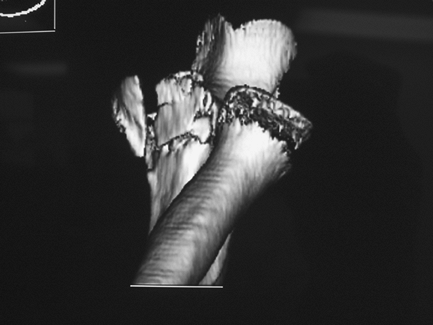

of plain tomography in this country. CT has the advantage of clearer

images and multiplanar views over plain tomography, although metal

artifact remains a limitation. Three-dimensional rendering of the elbow

joint is possible as well (Fig. 48-5). The

decreased slice thickness and helical image acquisition of the newest

scanners provide for improved clarity of reconstructed images.

Nonaffected bones can be digitally subtracted to allow improved

visualization of the involved area (Fig. 48-6).

This is especially helpful in complex coronoid fractures as well as for

preop planning for elbow malunion surgery. The injection of

Figure 48-6

Three-dimensional reconstruction of the elbow joint with digital removal of the humerus. The comminuted coronoid fracture is clearly seen. The abnormality of the radial head represents artifact rather than radial head/neck fracture. |